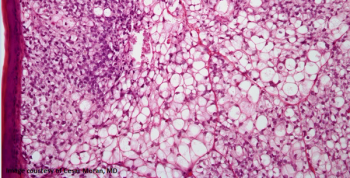

A 36-year-old patient presents with a liver mass, and a biopsy is performed. What is your diagnosis?